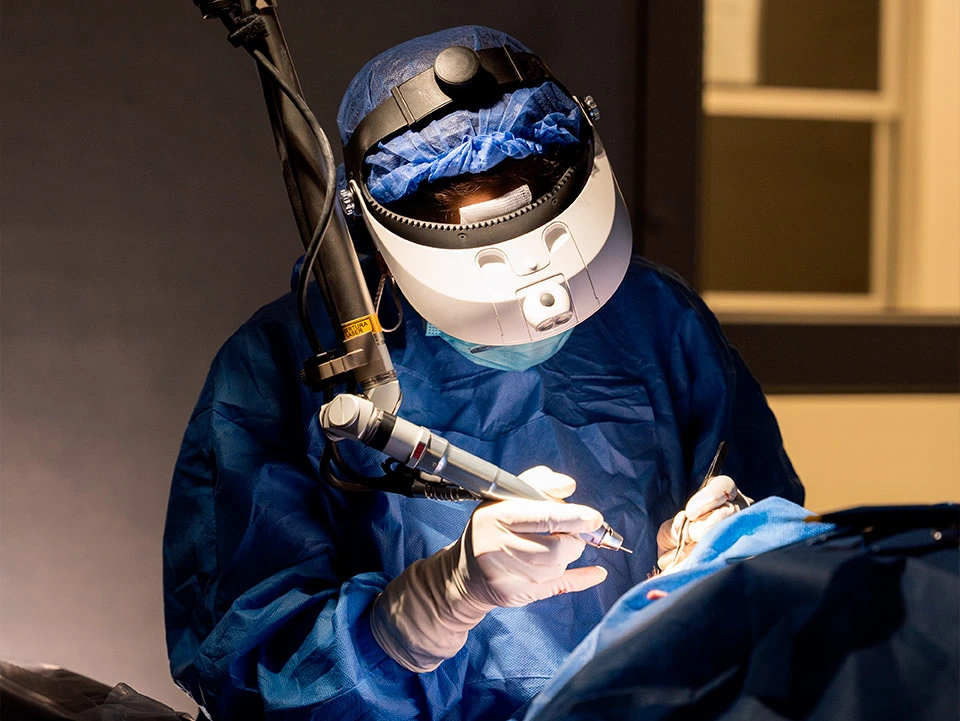

Quirófanos con la más moderna tecnología

Equipos para estudios oftalmológicos especializados